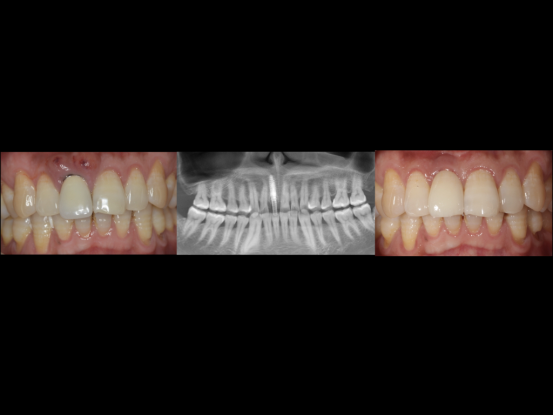

外伤冠折患者的种植修复